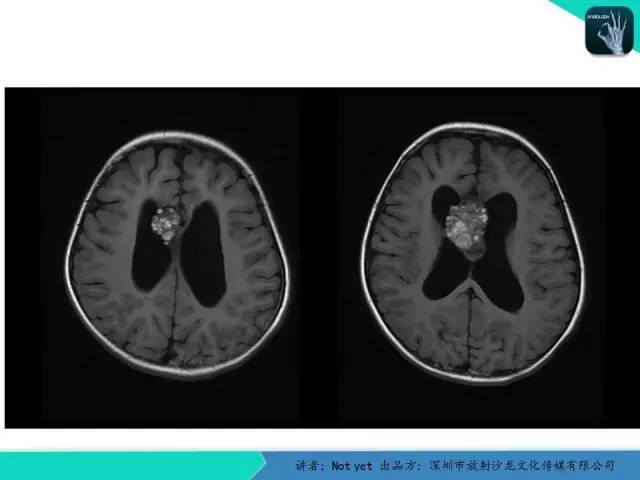

【病例】脑室内脉管瘤1例CT及MR影像诊断与鉴别